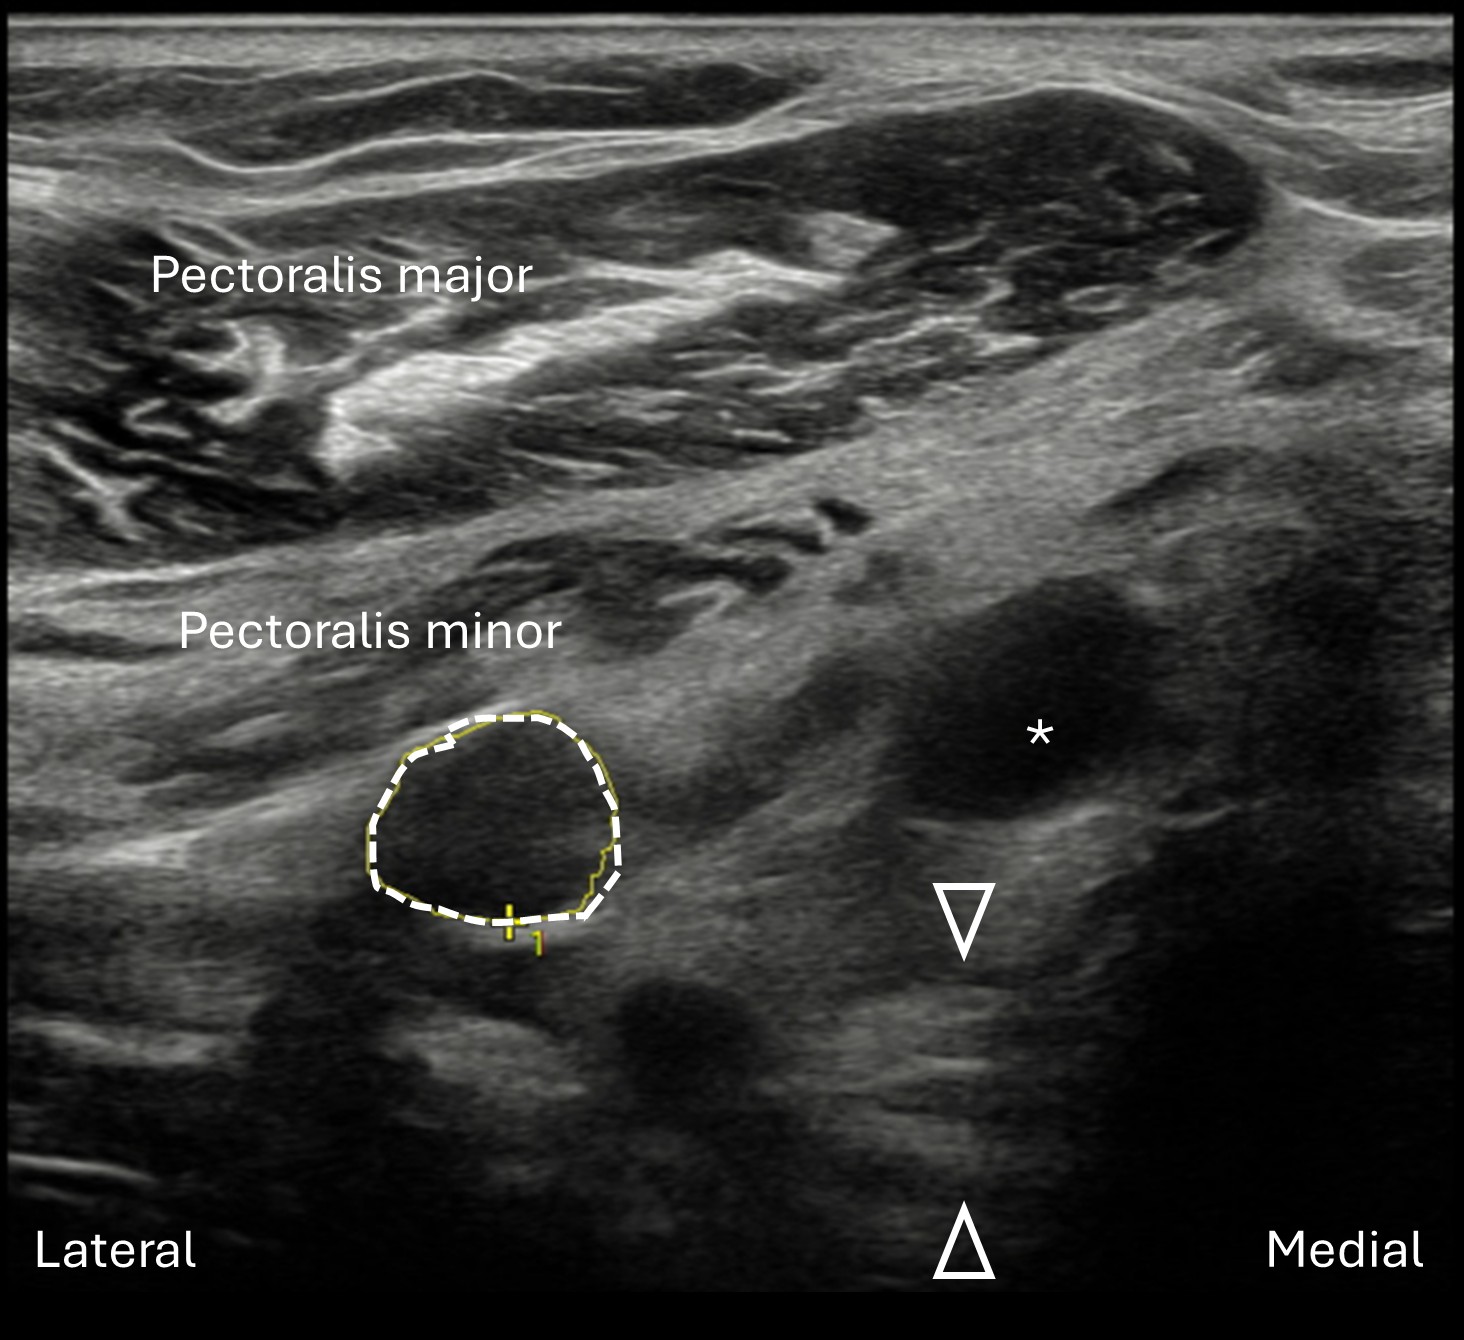

Labeled short axis view of the lateral cord of the right brachial plexus in the infraclavicular window. At this site there is focal enlargement of the lateral cord (dashed line, cross-sectional area 26.85 mm2), just distal to the cord transection (not visualized in this image). In this view, the lateral cord lies deep to both the pectoralis major and minor muscles, lateral to the axillary artery (asterisk). The posterior cord is seen deep to the axillary artery, marked by arrowheads.

Unlabeled short axis view of the lateral cord of the right brachial plexus in the infraclavicular view.